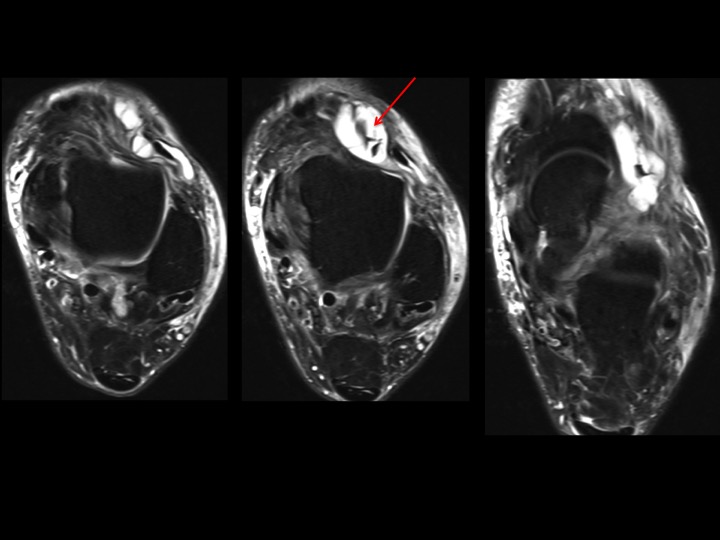

75M 4 months lateral ankle and foot pain

The Sinus Tarsi Bursa (of Gruberi) is situated between the lateral talar neck and the EDL. In this case its distended by fluid and contains thick cords of fat signal (red arrows). Would you consider this lipoma arborescens of the sinus tarsi bursa, even though the fat signal doesnt appear to branch? The majority of these bursae are soft and compressible. There is, however, atrophy and edema of the EDB muscle (blue arrow), suggesting anterior tarsal tunnel syndrome. Do you think this bursa is causing compression of the deep peroneal nerve? Reference article.